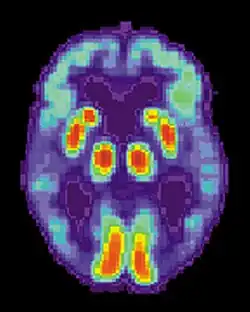

Hasta hace unos años, solamente era posible observar la acumulación de estas proteínas mediante el examen de los cerebros de los pacientes post mortem. Sin embargo, los recientes desarrollos en la tomografía por emisión de positrones (PET) han permitido a los científicos comenzar a visualizar su acumulación en pacientes que están vivos.

Las pruebas de imagen cerebral —Tomografía axial computarizada (TAC), Resonancia magnética nuclear (RMN), tomografía por emisión de positrones (TEP) o la tomografía computarizada por emisión de fotón único— pueden mostrar diferentes signos de que existe una demencia, pero no especifican de qué demencia se trata.[140]

En los casos en que estén disponibles imágenes neurológicas especializadas, como la TEP o la tomografía de fotón único, pueden servir para confirmar el diagnóstico del alzhéimer junto con las evaluaciones del estatus mental del individuo.[153]

Una nueva técnica, conocida como PiB PET, se ha desarrollado para tomar imágenes, directamente y de forma clara, de los depósitos beta-amiloides in vivo, con el uso de un radiofármaco que se une selectivamente a los depósitos Aβ.[155]